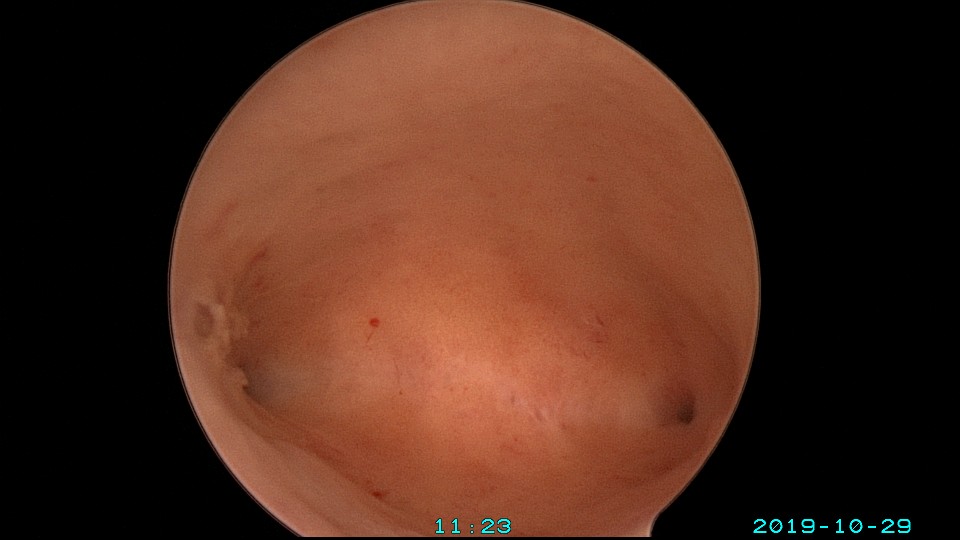

患者27岁,G2P0,人流1次,孕8周胎停清宫1次,绵阳市某医院造影发现宫腔粘连1+月,2019年10月初我院宫腔镜探查,发现宫腔右侧粘连,左侧输卵管开口可见,单极电切分粘,恢复宫腔形态,显露右侧输卵管开口。2019年10月底宫腔镜二探取球囊,宫腔形态正常,双侧输卵管开口可见。2021年10月自然妊娠,稽留流产,我院宫腔镜取胚,2022年再次自然妊娠,足月分泌。现33岁,G4P1。